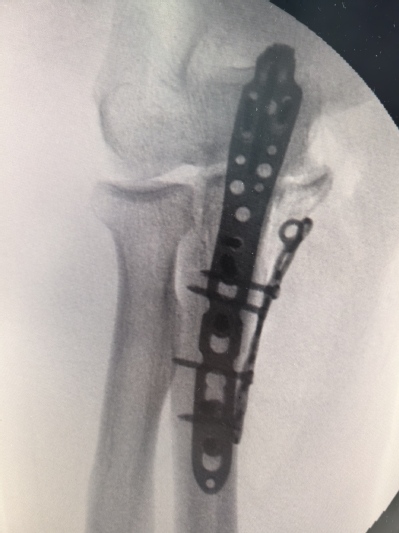

一名69岁男性,因不慎撞伤导致肘关节明显肿胀疼痛,不能活动,当即来亚洲色吧 就诊。行x线检查后示尺骨近段粉碎性骨折。经过吴卫东、黄晟医生仔细读片后诊断为经尺骨鹰嘴孟氏骨折。骨折断裂情况严重,尺骨鹰嘴、尺骨冠突骨块分离,同时存在肘关节内侧不稳定,病情复杂,手术难度非常大。

此次手术,借助先进3D打印技术,精确复制了患者骨折部位的骨骼结构,为手术提供了直观、详尽的参考。经过吴卫东、黄晟手术团队的努力,患者的粉碎性骨折得到了有效治疗,术后恢复良好。